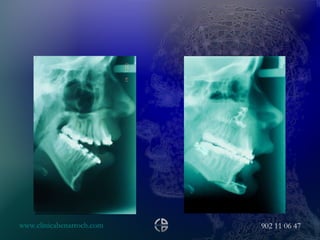

LR, F, 21.July, 2000 PROBLEM LIST Ocular surface disease Nasal deformity Lower third vertical augmentation Upper and lower lip deformity Maxillary transverse collapse AP chin deficiency Vertical chin augmentation SURGICAL PLAN 2 PHASES Maxillary assisted expansion Maxillary posterior impaction Mandible BSS Lip pasties Vertical reduction of the chin AP chin advancement

• #71 DO protocol Latency of 5 days Distraction Phase rate of 1 mm/d. a rhythm of 1-2 times per day Consolidation phase 8 to 12 weeks

• #72 X Rays After the latency period and after 12 weeks with the distractor extended advancement of 0.9 mm About the fixation period must be rigid enough to prevent the formation of fibrous tissue but not too rigid to prevent physiologic loading of the new bone

• #79 Maxillary assisted expansion with the same protocol of the last case, the orthodontics star to move the central incisors after 4 months

• #80 10 month after de expansion